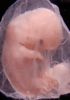

Carnegie Stage 19 (47 post-ovulatory days)

Most embryos at stage 19 are approximately 47-48 post-ovulatory days old and measure 17-20 mm in length. Distinguishing criteria for this stage include straightening of the trunk, the limbs extend nearly directly forward, toe rays are prominent, but interdigital notches have not yet appeared in the foot.

Although some of the photographs below show abnormal embryos, the animations and MRI slice images all depict normal embryos. Abnormal embryos are noted in the titles of the large photos when they are opened.

Photographs